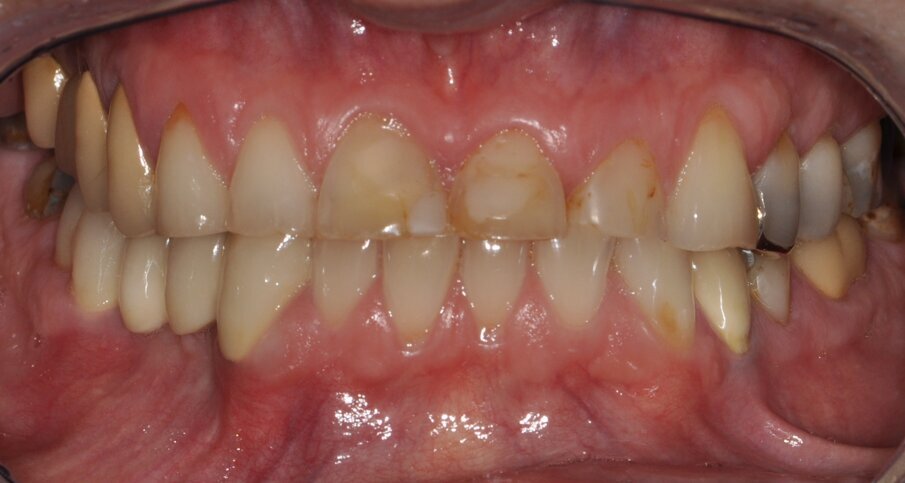

Fig. 1: Clinical baseline situation

A 55-year-old woman presented at the Department of Preventive Dentistry, Periodontology and Cariology of the University of Göttingen. The clinical and radiological examination revealed an adult dentition that had been insufficiently treated with fillings and dental restorations and exhibited a loss of vertical dimension of occlusion (Figs. 1 and 2). Insufficient restorations (secondary caries) were found on teeth 24, 25, 26, 27, 37, 38, 35, 47, and 48. The existing bridge (17–15, 14) was insufficient due to extensive ceramic fractures. Part of the hard tissue of the upper maxillary incisors with their — sometimes extensive — composite restorations had been lost to attrition and vestibular erosion. The endodontic treatment of tooth 34 was adequate, while tooth 46 required a primary endodontic treatment due to an irreversible pulpitis. All other teeth were vital and free of symptoms. The periodontal findings showed moderate gingivitis (periodontal screening index < 3 in all sextants). Teeth 13, 23, 24, and 43 additionally exhibited vestibular gingival recessions.